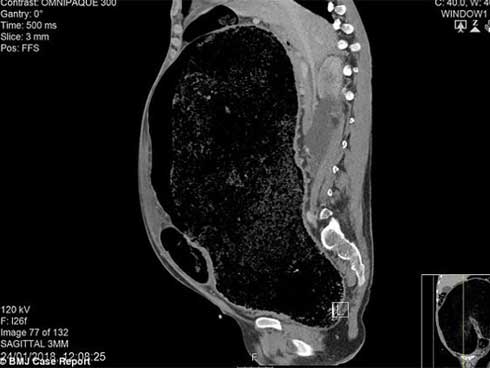

Bé tên Huỳnh T.Th. (2 tháng tuổi, ngụ Vĩnh Long), mắc các bệnh bẩm sinh: suy dinh dưỡng, viêm đại tràng, phình đại tràng bẩm sinh, sứt môi, hở hàm ếch…

Bé Th. nhập viện trong tình trạng nhiễm trùng, viêm ruột, suy dinh dưỡng, mắc nhiều bệnh bẩm sinh cùng lúc, nguy cơ cao. Sau khi tiếp nhận, bệnh viện đã điều trị nội khoa, nâng đỡ tổng trạng bé, sau đó phẫu thuật phình đại tràng cho bé.

Sau 1 giờ phẫu thuật, ca mổ thành công, các bác sĩ đã cắt bỏ đoạn ruột vô hạch dài 13 cm, hạ đại tràng xuống hậu môn cho bệnh nhi. Hiện bé được chăm sóc tích cực sơ sinh, đợi đến khi sức khỏe hồi phục sẽ được mổ tiếp.